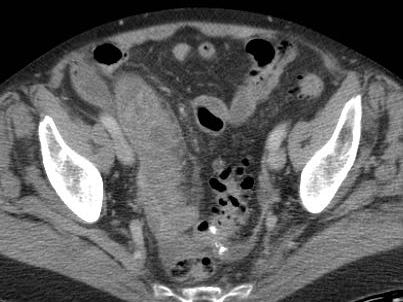

Ở bệnh nhân này, siêu âm cho thấy lượng lớn mô mỡ viêm (*) và hồi tràng dày thành, biểu hiện quá trình bao bọc thành công tình trạng thủng (sắp xảy ra) của ruột thừa (mũi tên).

Lưu ý sỏi phân vôi hóa (mũi tên trên CT) trong ruột thừa ở mức cao hơn.